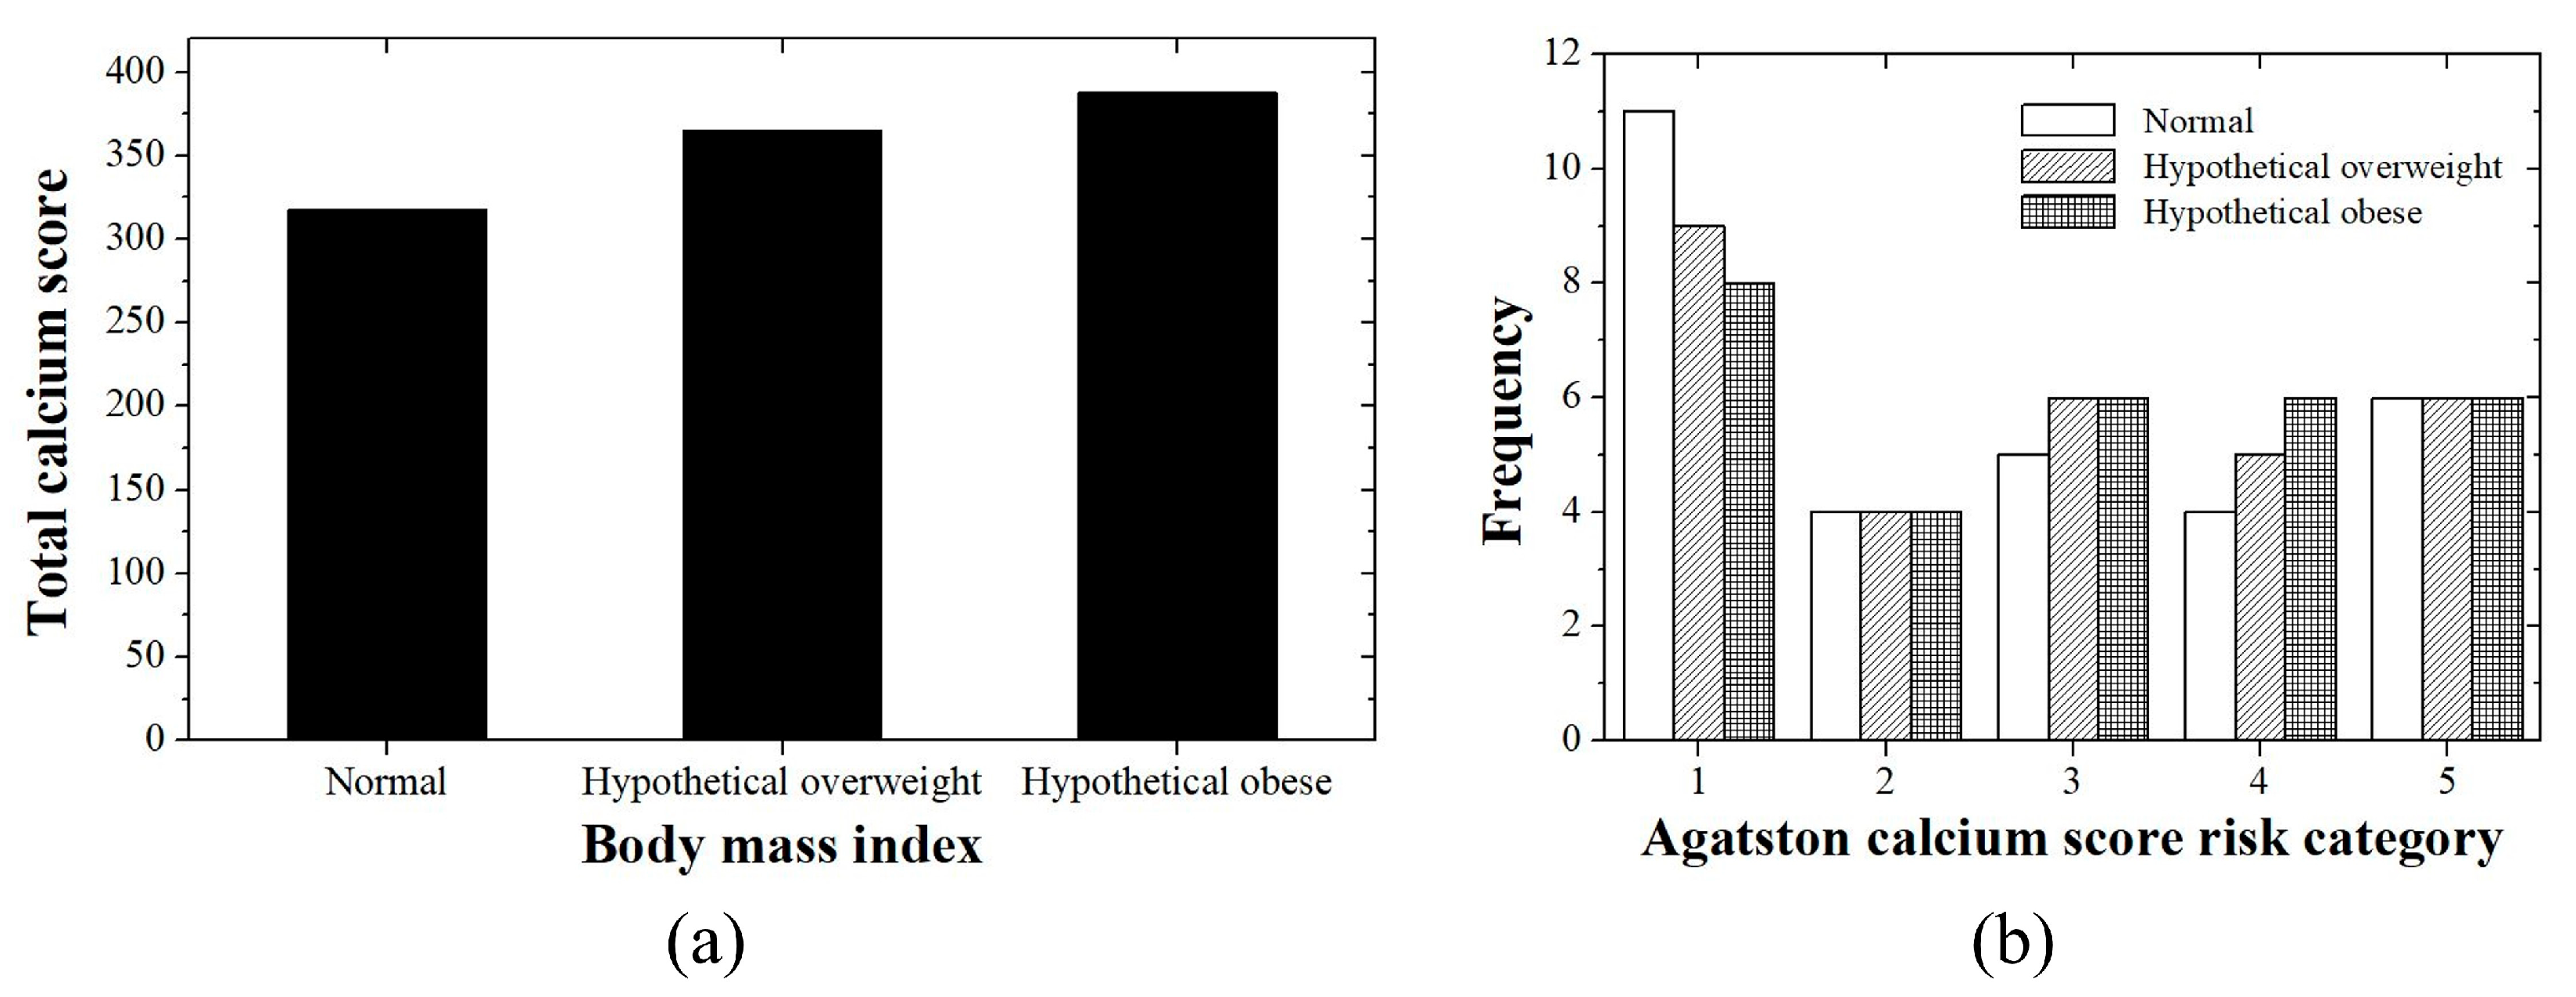

2.6. Study Designs

3. Results

3.1. Patient Study

3.2. Phantom Study

4. Discussion